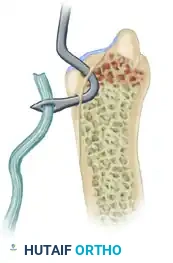

Figure: Dislocation of the radial head demonstrating a ruptured annular ligament. In acute settings, this ligament can often be sutured satisfactorily.

Step 3: Ligament Repair or Reconstruction

* Primary Repair: If the tissue quality is robust, the annular ligament is repaired directly to its ulnar footprint using suture anchors or transosseous sutures.

* Reconstruction: In chronic cases (greater than 4-6 weeks) where the annular ligament is contracted, attenuated, or absent, reconstruction is required. A strip of autologous fascia lata or a slip of the triceps tendon can be utilized.

Figure: If primary repair is impossible, the annular ligament can be reconstructed using a strip of fascia lata passed around the radial neck.

- The graft is passed circumferentially around the radial neck and secured to the anterior and posterior margins of the sigmoid notch through drill holes.

- Tensioning must be precise: tight enough to prevent subluxation, but loose enough to permit full, unhindered pronation and supination.